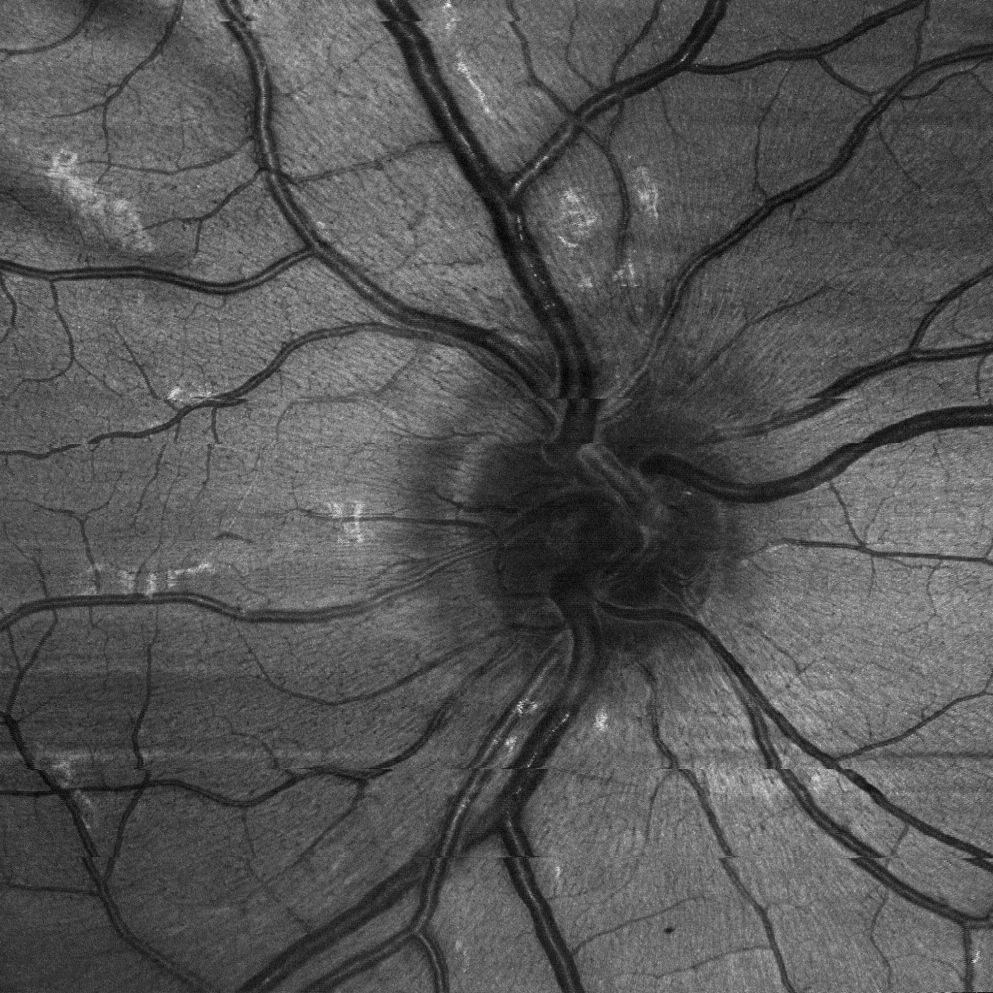

Opticent Health

Systems Engineer Opticent Health

Oct 2025 – Present Full-time

• • Fully redesigning and reducing the footprint of OCT imaging systems for metrology and human research.

• • Researching and automating liquid lens calibration to accelerate and improve system calibration during assembly.

• • Standardizing, documenting, and designing wire harnesses for cutting-edge visible-light OCT imaging systems.

• • Aiming to take our systems to the clinical level.